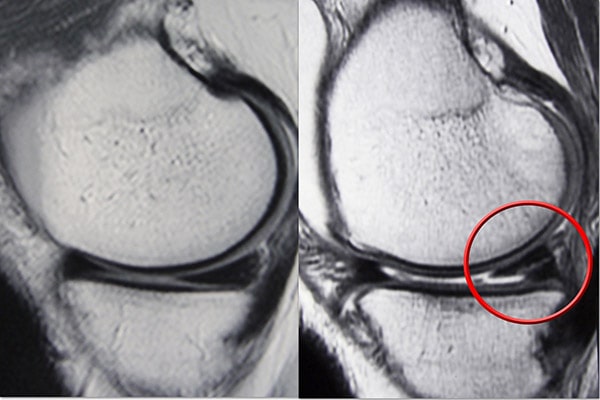

磁共振成像 (MRI) 掃描。  MRI 掃描可評(píng)估膝關(guān)節(jié)的軟組織,包括半月板、軟骨、肌腱和韌帶。

MRI 掃描顯示(左)正常的半月板和(右)撕裂的半月板。撕裂可以看作是穿過(guò)半月板黑色主體的白線